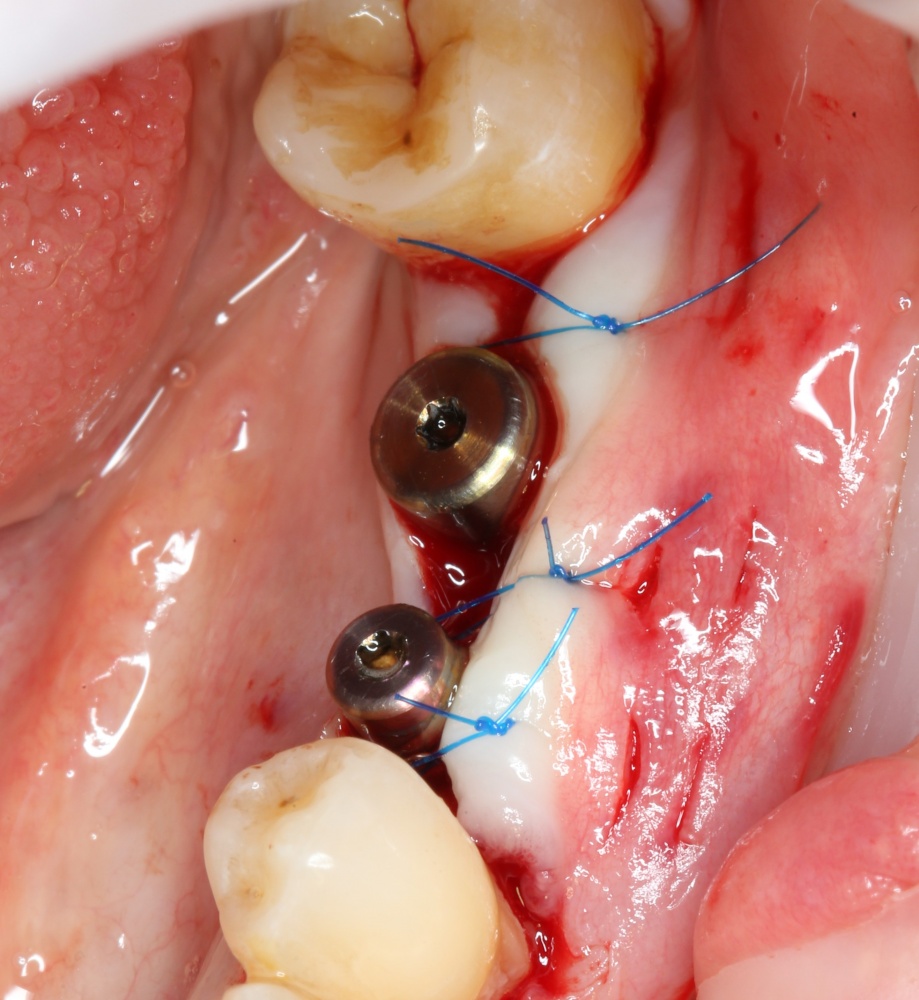

Теперь делаем разрез и открываем импланты:

A09A6620 (2) A09A6621 (2)

На фотографиях хорошо видно, какие изменения произошли с областью операции за четыре месяца. Пересаженный костный блок интегрировался настолько хорошо, что частично заросли заглушки имплантов. Такое нередко происходит, именно поэтому в подобных случаях я предпочитаю импланты с конической ортопедической платформой — их легче открывать.

Нам остается просто поставить формирователи десны:

A09A6628 (2) A09A6629 (2)